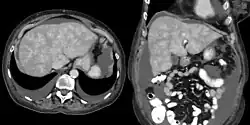

It is diagnosed with laboratory testing, including liver function tests, and radiology imaging, including ultrasounds.[3][4]